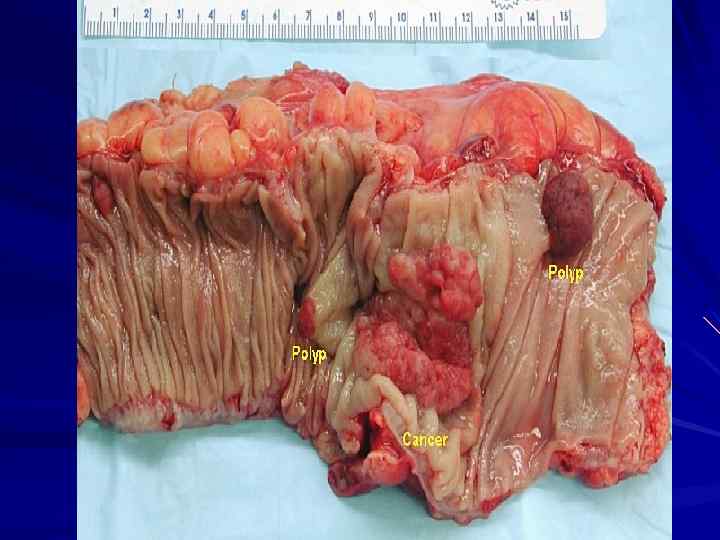

РАК ТОЛСТОЙ КИШКИ

РАК ТОЛСТОЙ КИШКИ

РАК ТОЛСТОЙ КИШКИ

РАК ТОЛСТОЙ КИШКИ